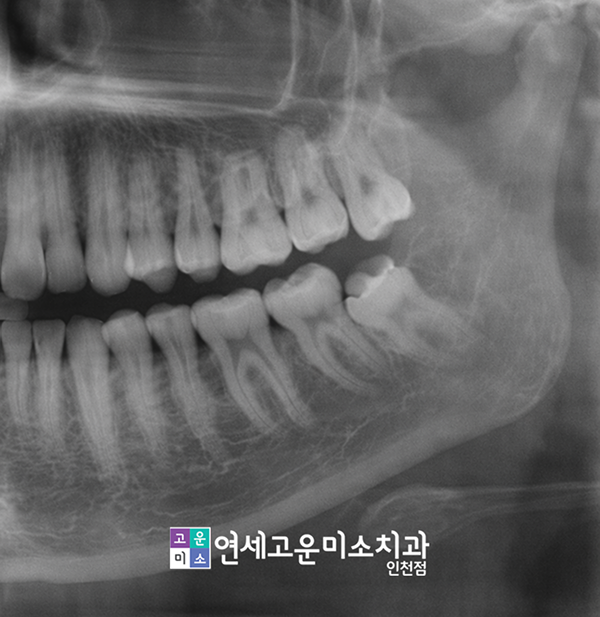

Q. 보통 어떻게 진단하나요?

치과에서는 보통 엑스레이로 치아가 신경과 얼마만큼 가까운 위치인지 파악합니다.

다만 경우에 따라 3차원적 진단지표가 필요하다면 구강 전용 3D-CT를 통해서 더 자세히 진찰합니다.